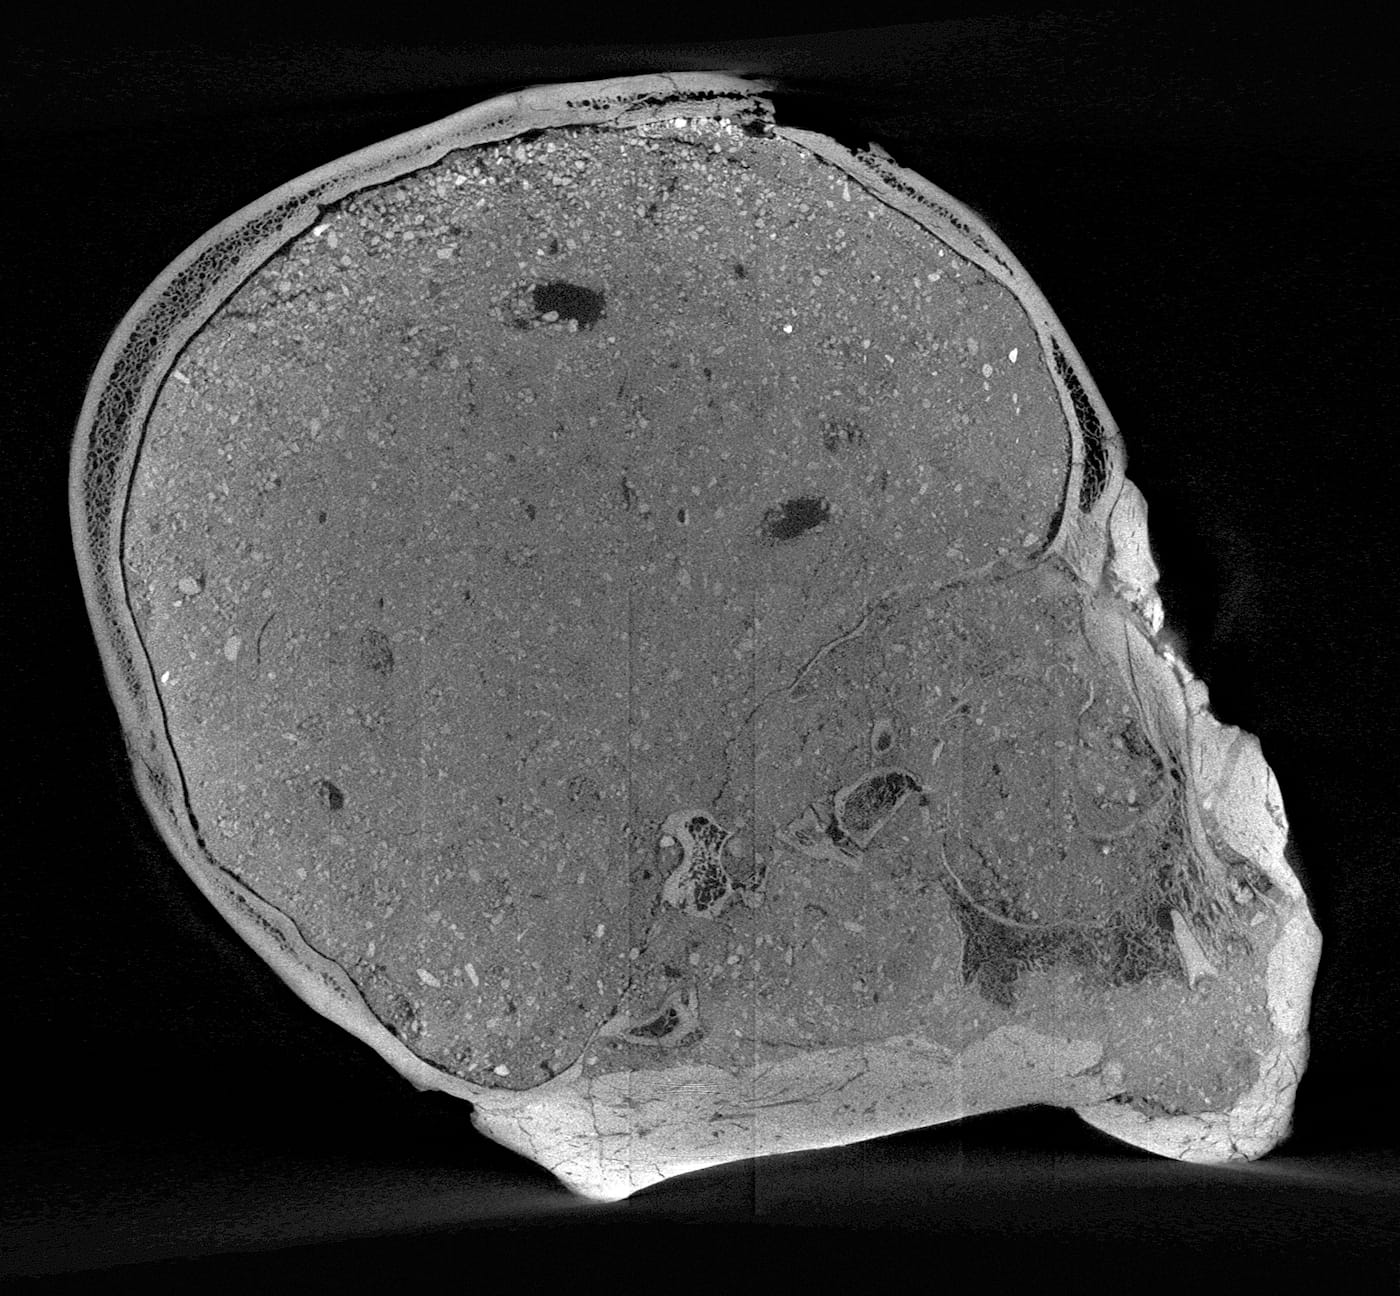

We now have an idea of what this particular individual looked like, as experts at the Natural History Museum’s Imaging and Analysis Center have used micro-CT scanning to create a 3D facial reconstruction of the Jericho Skull. The head, which is currently on display, depicts a man in at least his 40s who likely underwent ritual skull reshaping when he was younger, as suggested by the slight broadening of his head across the back.

The imaging team conducted its own sculptural process, but one, of course, aided with the latest digital technologies. Experts first digitally separated the shape of the skull bones from the overlying plaster then converted data from a micro-CT scan to create a 3D-printed model of the cranium. As the mandible was not present, the team added a lower jaw constructed based on data from other known examples of human mandibles of similar age and geographic origin. The face was then built over the skull model — this time, in a more traditional sculptural process: experts used clay and wax to build features from the bone-up, muscle by muscle, creating every anatomical detail before topping it off with a clay layer of tissue and skin. Finally, they made a mold of the head from which the displayed face was cast in Jesmonite — essentially a mixture of gypsum and acrylic resin.